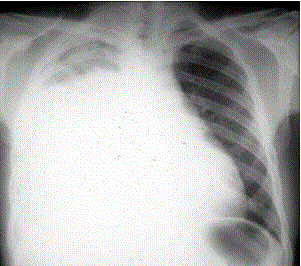

患者男,34岁。进行性胸闷、气促1个月余,伴有干咳、右胸隐痛以及消瘦,无咯血、发热、盗汗、潮热等。(提示 胸部X线检查如图所示)为进一步明确病...

问题 患者男,34岁。进行性胸闷、气促1个月余,伴有干咳、右胸隐痛以及消瘦,无咯血、发热、盗汗、潮热等。 (提示 胸部X线检查如图所示) 为进一步明确病因诊断,下一步检查包括:(提示 患者既往有“慢性胃炎”史10年,未详细检查过,近半年有上腹隐痛、食欲减退、体重减轻。无吸烟及酗酒史,否认肝炎、肺结核病史。)

选项 A.胸部CT检查 B.肺功能检查 C.心电图检查 D.胃镜检查 E.胸膜活检病理检查 F.胸腔积液沉淀找癌细胞 G.胸腔积液沉淀找抗酸杆菌 H.血清ANA、抗dsDNA抗体、抗Sm抗体检测 I.胸腔积液细菌培养 J.痰找抗酸杆菌检查 K.超声心动图检查 L.PPD皮试

答案 ADEF